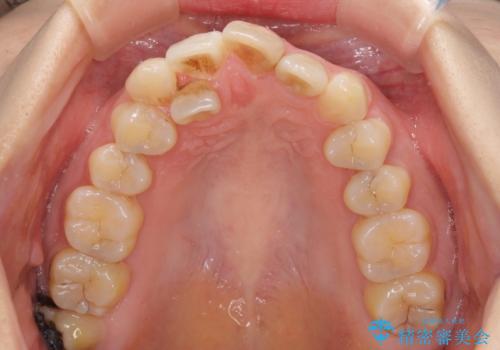

- 重なった前歯を邪魔に感じ、汚れも溜まりやすいことを気にして来院された患者様です。

右上前から2番目の歯が内側に転位しているため、上顎の正中は右にずれていました。

右上4番目の歯を抜歯し、上顎裏側に補助装置を装着して左の歯列全体を後方に移動させながら、正中を合わせるようにして行くこととしました。

内側に転位していた歯はきれいに歯列に収まり、清掃性が著しく改善しました。